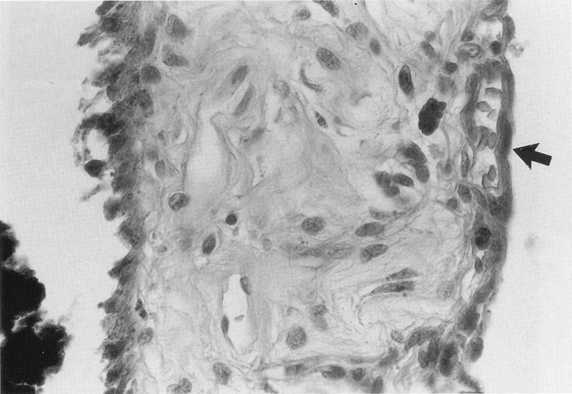

2. The presence, extent, and pattern of tumor necrosis were noted. The pattern of necrosis was identified as involving individual cells (Fig. 1) or as patchy when there were areas of necrotic cells scattered throughout the tumor (Fig. 2), or as geographic when confluent areas of the tumor were necrotic (Fig. 3). In each case, the extent of necrosis in the examined section was also recorded as <25%, 25-50%, >50-75% or >75% (Fig. 3).

Figure 1

FIG. 1. Individual cell necrosis, reflected by pigment laden macrophages in an eye treated with episcleral radioactive plaque therapy (RPT). (Hematoxylin and eosin; X200, 86-1428.)